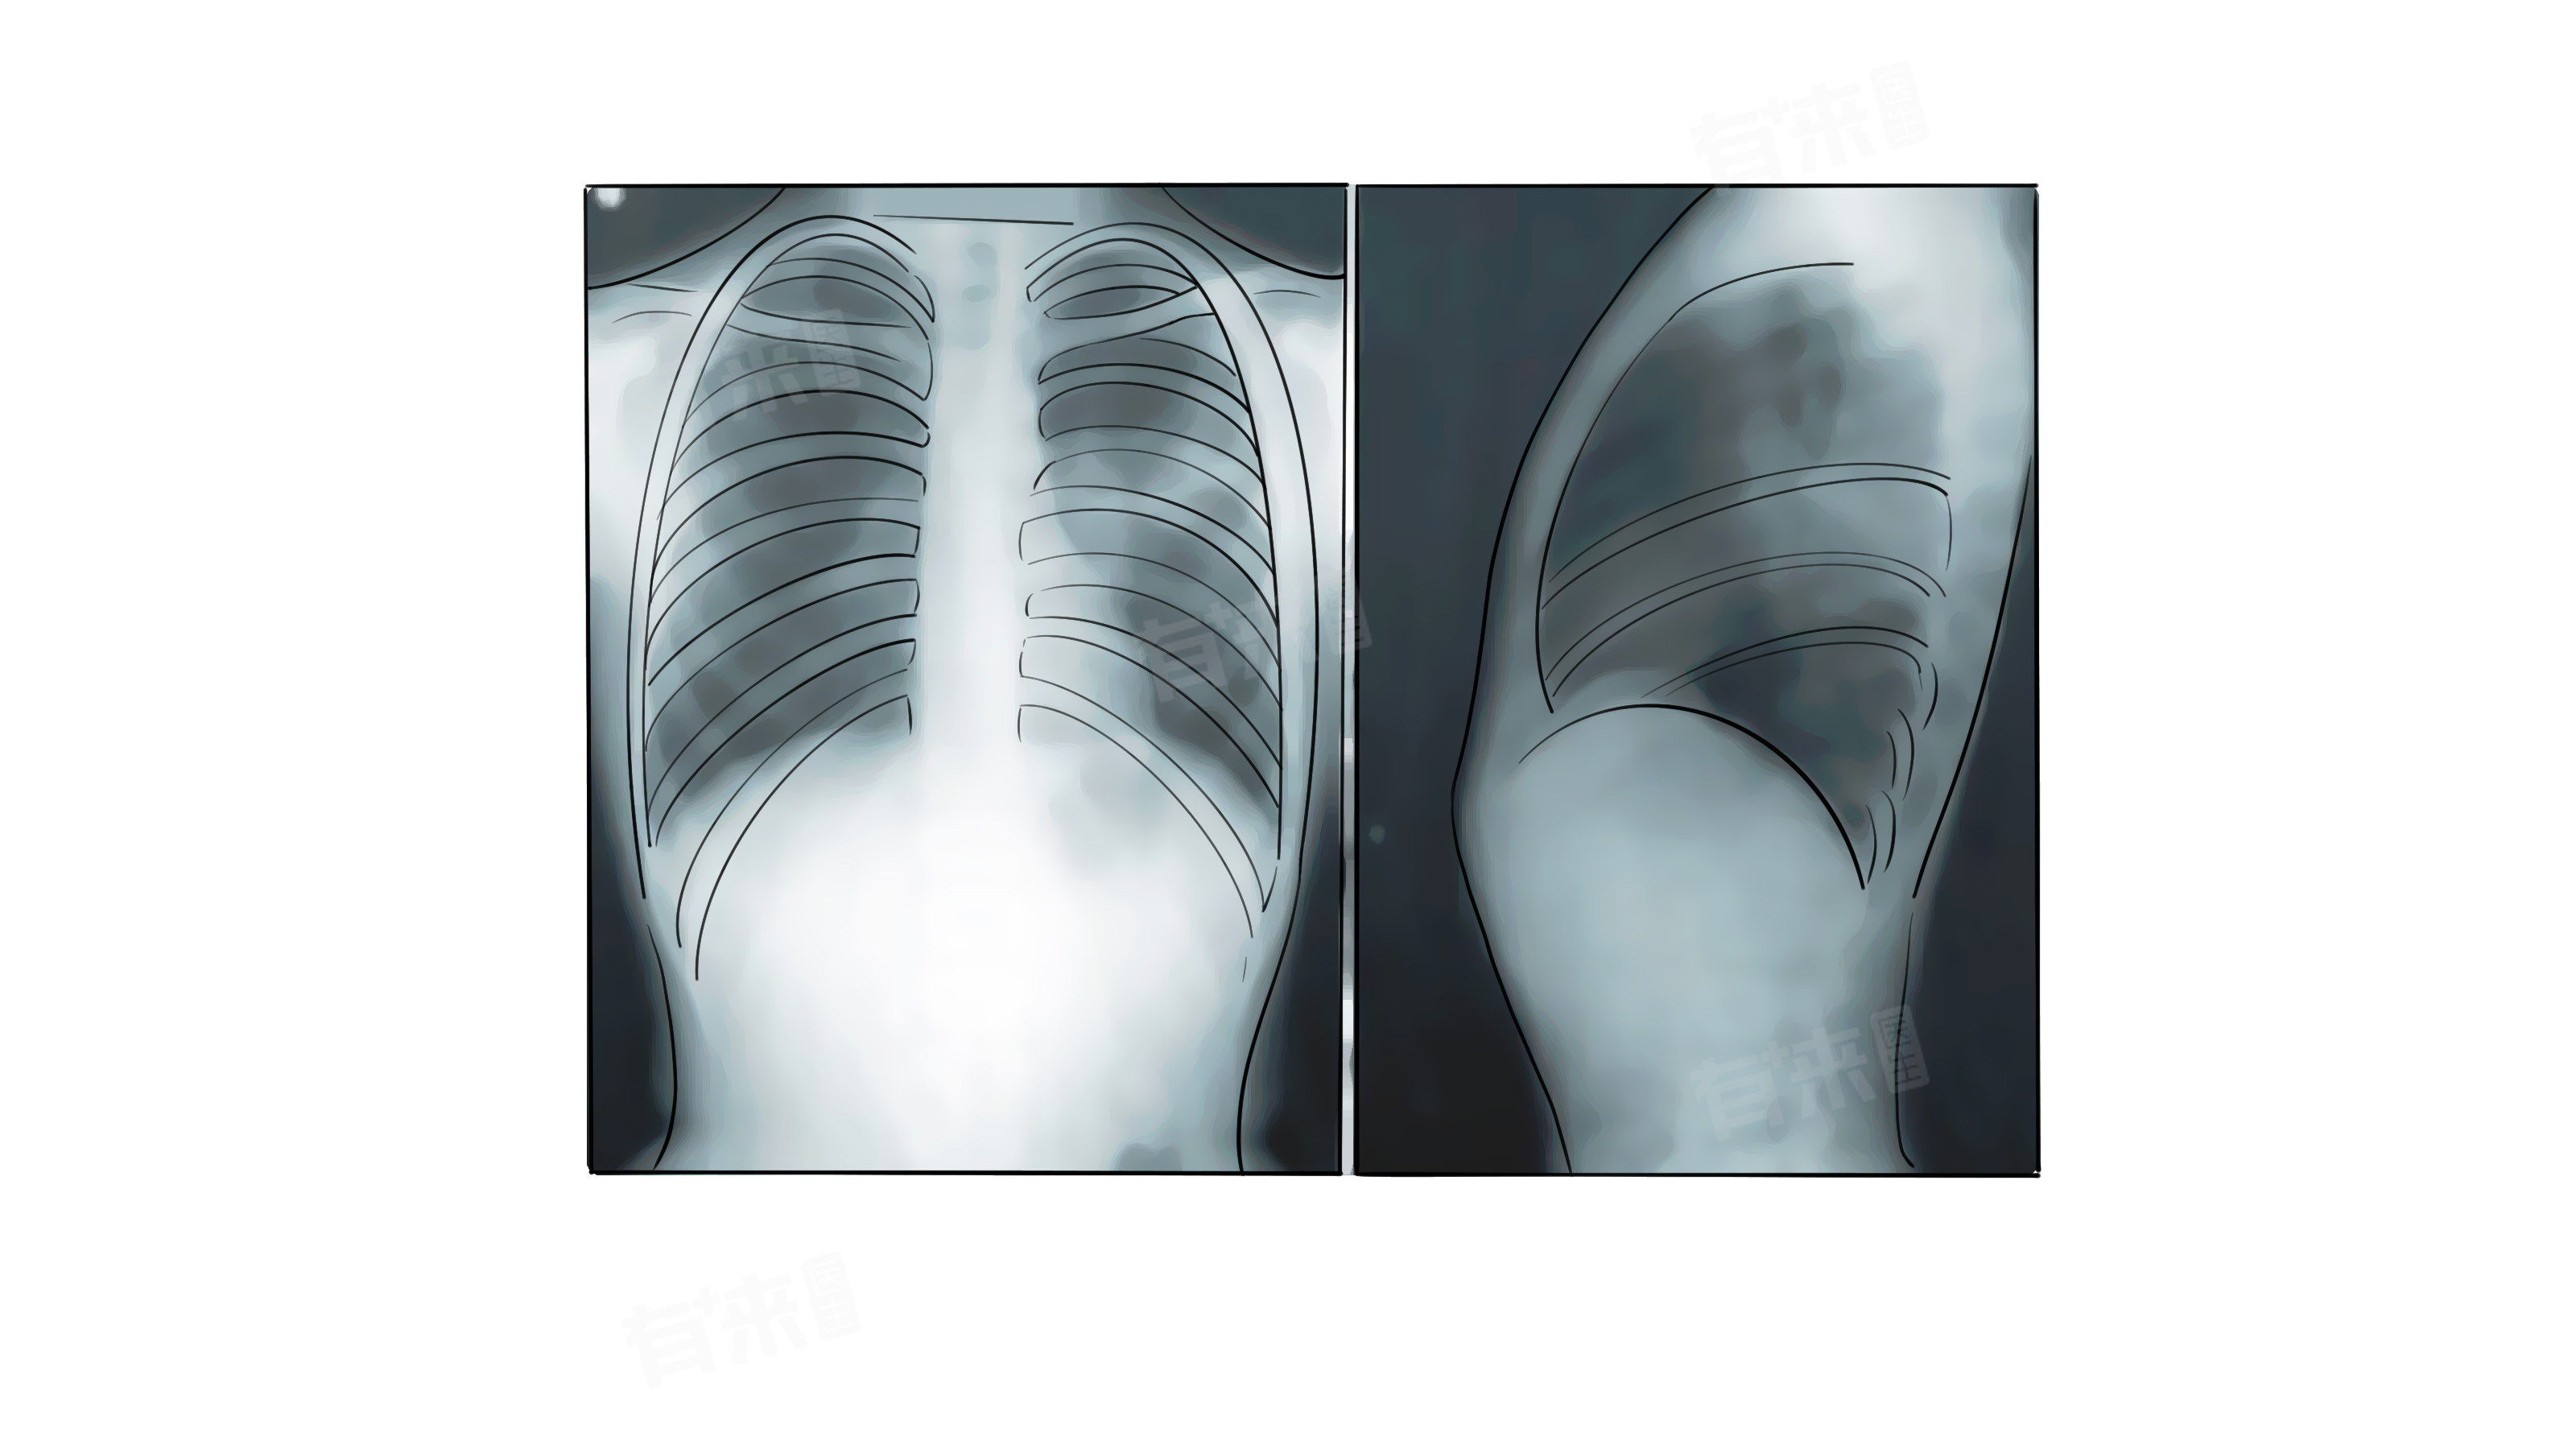

1、解剖位置:肋膈角是肋骨与膈肌在胸腔底部形成的夹角,正常情况下此处结构清晰,无异常阴影或积液等,在胸部 X 光片或CT图像上,可以清晰地看到肋膈角的形态。

2、影像学表现:当描述为双肋膈角锐利时,意味着在影像上该区域边界清晰,角度明显,表明胸腔内没有积液、积气或其他异常病变累及此部位。

3、临床意义:双肋膈角锐利是正常的表现,无需特殊处理,但如果出现肋膈角变钝或消失,则可能提示有胸腔积液、胸膜炎等疾病。对于某些疾病的患者,在治疗过程中观察肋膈角的变化也有重要意义,如果原本异常的肋膈角在治疗后逐渐恢复锐利,说明病情在好转。